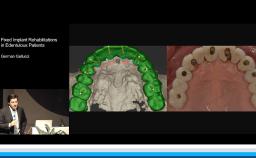

Part one of a two-part presentation gives a comprehensive overview of how to treat complex cases using an interdisciplinary approach in implant dentistry. From the prosthodontist’s point of view, the workflow starts with careful prosthetic planning by the use of wax-ups or set-ups, and in some cases orthodontic pretreatment is indicated. This lecture demonstrates how the prosthetic planning is then transferred by surgical templates to facilitate the correct 3D prosthodontically driven implant placement. In this workflow, the provisional prosthesis conditions the soft tissue in order to optimize esthetics prior to finalizing the prosthetic rehabilitation. This lecture includes a series of ‘Prosthetic Rules’ to serve as benchmarks for effective prosthodontically driven treatment.

- describe the workflow of careful prosthetic planning, surgical templates during implant placement, provisional prosthesis with soft tissue conditioning, and final rehabilitation